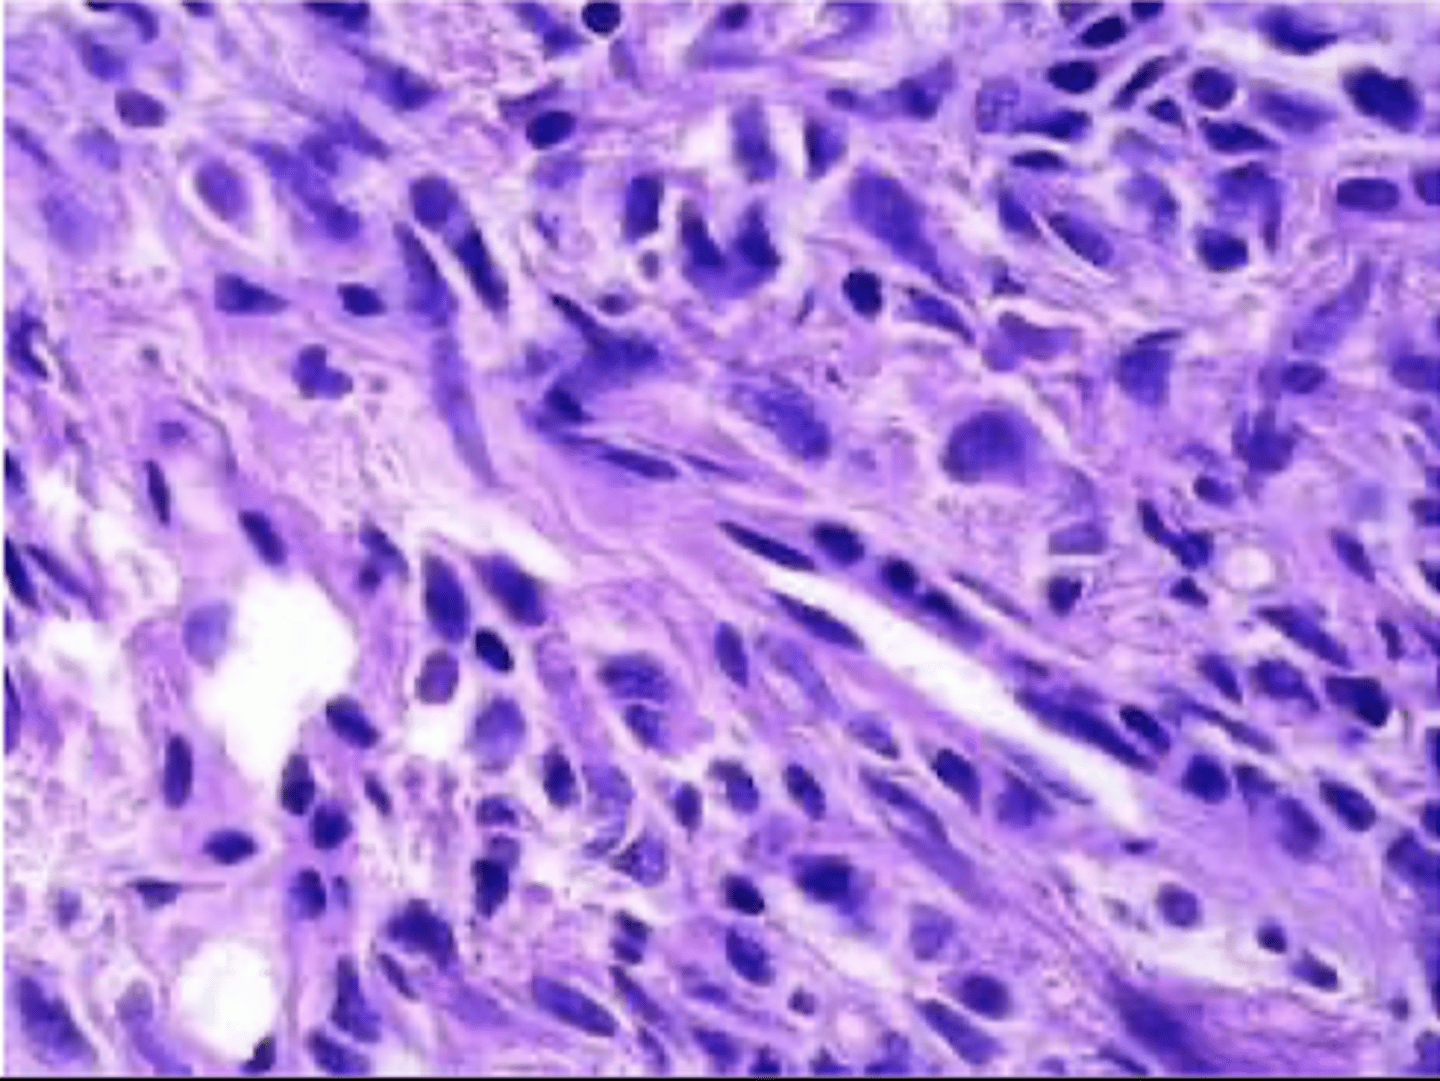

angiosarcoma

malignant endothelial neoplasm

appearance of angiosarcoma

starts as small papule

progresses to large, fleshy red tan to gray white lesions with blurred margins, necrosis, hemorrhage

CD31 (vWF)

endothelial origin

angiosarcoma